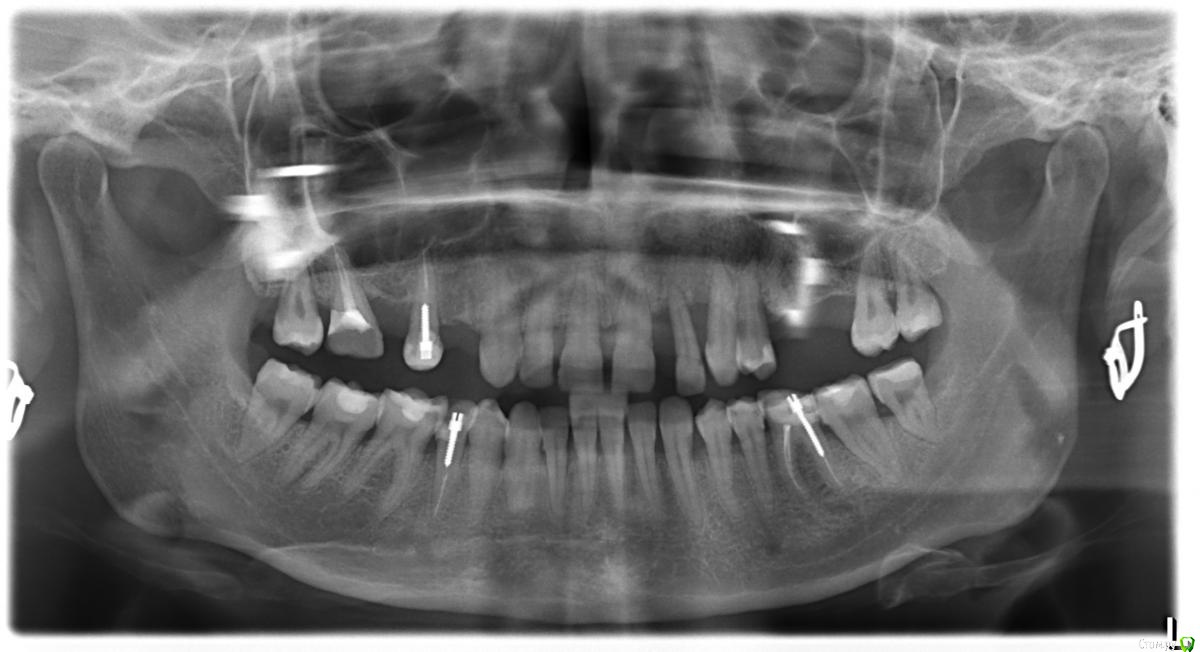

Dorin Опубликовано 28 марта, 2016 Поделиться Опубликовано 28 марта, 2016 Добрый день! Посмотрите, пожалуйста, снимок! Что возможно сделать в моей ситуации (интересует левая сторона)? С правой, вроде бы, хирурга ничего не смутило: ставить имплант + коронки, там, где это необходимо. А вот слева...я наивно полагала, что возможно просто удалить травмированный зуб и поставить на его место имплант, оказалось, что все гораздо печальнее...Доктор предлагает удалить слева 3 зуба и поставить конструкцию из 4-х имплантов и 1 коронки + синус-лифтинг, при условии, что ортопеды возьмутся спасать передний резец. На ваш взгляд, возможно ли в этой ситуации какое-то другое решение проблемы?Заранее благодарю за ответ! Ссылка на комментарий

Bier Опубликовано 29 марта, 2016 Поделиться Опубликовано 29 марта, 2016 можно поставить меньше имплантатов и обойтись без синуслифтинга, но зубы надо удалять, Док прав. Ссылка на комментарий

Bier Опубликовано 30 марта, 2016 Поделиться Опубликовано 30 марта, 2016 синуслифтинг - это не просто наращивание кости, это поднятие пазухи, пазуха у вас низко только в области 6го зуба, можно туда имплантат не ставить, сделать подвесной зубик.Но я бы сделал синуслифтинг. Ссылка на комментарий

red_butler Опубликовано 31 марта, 2016 Поделиться Опубликовано 31 марта, 2016 И еще: все-таки, на ваш взляд, тот вариант, что рекомендовал мой хирург является предпочтительным, т.е. 4 импланта+1 коронка? Можно и тремя обойтись. В первой (на косультации у хирурга была в ней) работают с имплантами superline, во второй (туда на консультацию пока только записалась) работают с semados, стоит ли делать выбор, исходя из этого? Нет, искать стоит врача.Покажите фото зубов с десной, и фото улыбки. Ссылка на комментарий